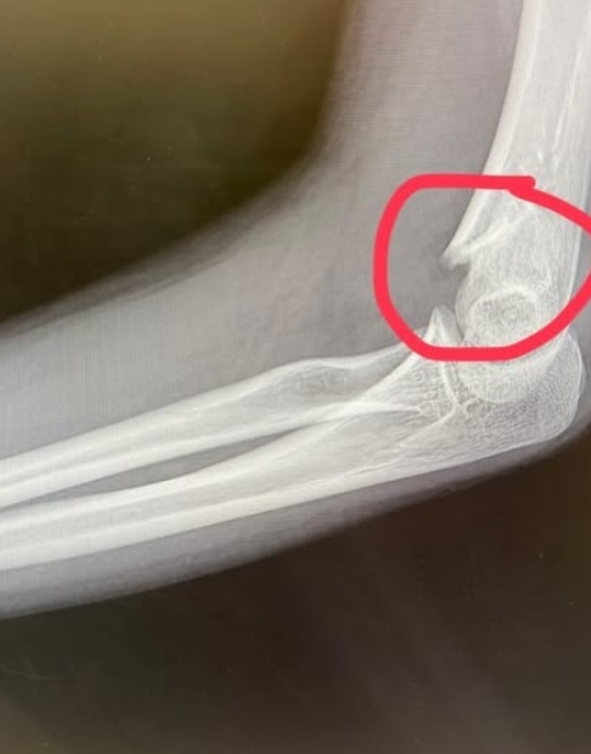

แฟน ๆ และคนในวงการบันเทิงร่วมส่งกำลังใจให้น้องอินเตอร์ รุ่งรดา รุ่งลิขิตเจริญ ดาราเด็กชื่อดัง หลังประสบอุบัติเหตุลื่นล้มขณะเข้าเรียนคลาสเต้นในช่วงเย็นวันที่ 1 ธันวาคม 2568 ทำให้แขนหักและต้องเข้ารับการรักษาเร่งด่วนที่โรงพยาบาล โดยแพทย์เตรียมผ่าตัดดามเหล็กเพื่อรักษาอาการบาดเจ็บ

น้องอินเตอร์ได้โพสต์ข้อความผ่านอินสตาแกรม inter_rungrada ถึงเหตุการณ์ที่เกิดขึ้นว่า "อุบัติเหตุเกิดขึ้นได้ทุกเวลา มาเรียนเต้น…แต่ลื่นล้ม แขนหัก เศร้าเลยค่ะ ขอโทษกองละครทุกกองด้วยค่ะ จะรีบหายไวไวนะคะ และขอบคุณครูจ๋าครูฝ้ายที่อุ้มมาส่งขึ้นรถ ตอนนี้รอผ่าตัด ดามเหล็ก ขอบคุณทุกคนที่เป็นห่วง ส่งกำลังใจมาให้น้องอินเตอร์นะคะ"